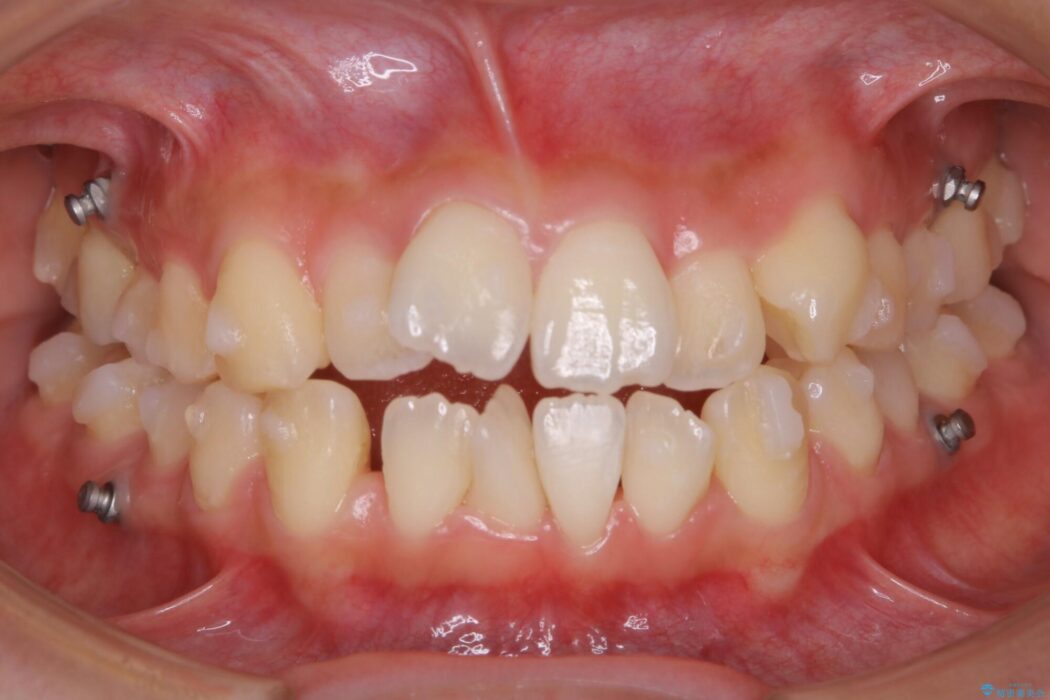

特に前歯部分に90度近く捻転した歯、斜めに生えている歯などによる歯列のがたつき、正中のズレが目立っていました。

奥歯から遠心移動とディスティング(歯の側面を僅かに削る)を行うことで歯列を整えるスペースを確保し、患者様のご要望からインビザライン装置での矯正を計画しました。

マイクロインプラントとは

マイクロインプラントとは矯正治療で使用する小さなネジのことです。

このネジを支点とし歯を引っ張ることで効率的に動かすことで、治療期間の短縮や従来の矯正治療では難しかった動きも対応が可能になります。

埋入することによる痛みはほとんどありませんが、数日ほど違和感を感じる方はおられます。また治療が終了次第、簡単に取り外すことができます。